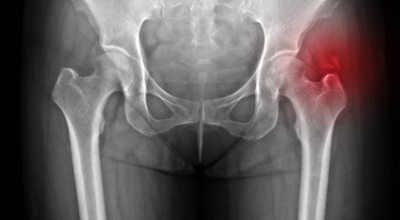

고관절염은 고관절에 발생하는 관절염을 말하며 고관절의 연골이 닳게 되면서 뼈와 뼈가 서로 부딪히며 통증을 유발하게 됩니다. 고관절염 초기 증상으로는 사타구니 부위가 불편하게 느껴지며, 무리하면 통증이 발생할 수 있고 관절염 증상이 악화되면서 사타구니에서 느끼던 통증이 허벅지와 엉덩이 통증으로 이어지기도 하는데요 고관절염 통증 증상으로 초기에는 허리 통증이 나타나 허리 질환과 혼동하기 쉬우며 특히 척추질환이 있는 사람은 고관절 통증 증상과 마찬가지로 엉덩이, 다리 통증이 동반되기 때문에 더욱 헷갈리는 경우가 많다고 합니다.

또한 고관절이 있는 부위는 근육과 지방으로 덮여 통증을 제대로 감지하기 어려워 고관절 통증 증상으로 인한 질환을 발견하기 쉽지 않은 경향이 있습니다. 따라서 평소에 사타구니 통증이 지속되거나 특히 양반다리를 할 때 통증이 있다면 고관절 질환을 의심해볼 수 있으며 격렬한 운동을 즐겨하는 사람이나 체중이 많이 나가는 사람들에게는 퇴행성 고관절염이 생길 가능성이 있으므로, 이러한 경우 허리 통증이 느껴지면 퇴행성 고관절염을 의심해보고 적절한 검진을 받아보는 것이 좋습니다.